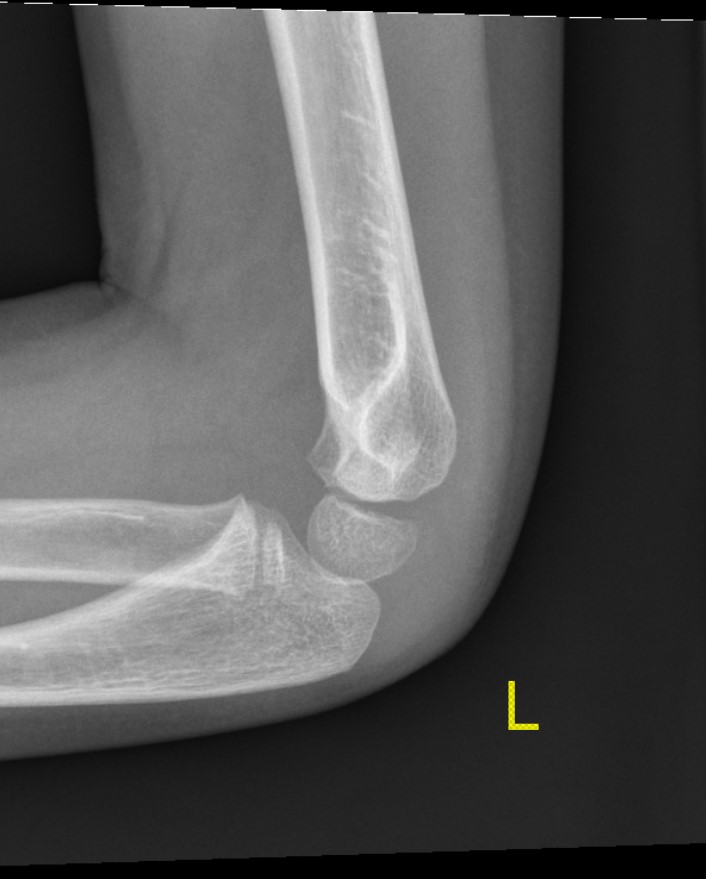

X-ray

Undisplaced

- typically metaphyseal flake

- looks minimally displaced on AP and lateral

- perform an internal oblique x-ray to exclude displacement

Injured left elbow v injury right elbow

Open reduction of displaced lateral condyle in left elbow